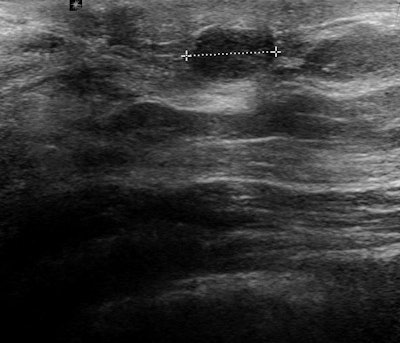

Ultrasound is the more simple and accessible technique to image this area. It's important to remember benign lesions are much more frequent than any other (infiltrating, noninfiltrating, or even premalignant), and thus ultrasound becomes useful for diagnosis as well as to control the evolution. Another reason ultrasound is the method of choice is that it's cheaper than MRI.

"The main advantage of ultrasound for nipple/areolar region is the chance to do a physical examination combined with the results of the technique in a single session," he continued. "The special tricks and facts to consider about the technique and a thorough knowledge of the pathology of nipple and areola will help the radiologist in achieving a high performance in the approach to a clear diagnosis in this part of the breast."

It is very important that radiologists are not afraid to check the nipple and areola under ultrasound in patients with problems in this area. It is necessary to convince the clinicians that ultrasound will add many facts to refine the diagnosis and treatment for their patients, he noted.